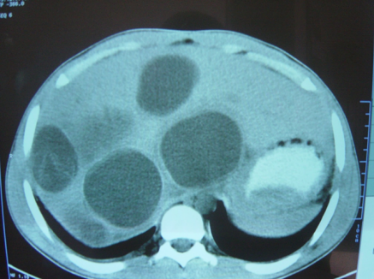

Morfologiyası

• Əksər hallarda (70%) çoxsaylı olur və qaraciyərin hər iki payını tutarlar.

• Ölçüləri bir neçə millimetrdən bir neçə santimetrə qədər dəyişə bilər.

• Tək şişlər adətən sağ payı tutar.

• Əksəriyyəti arerial qanla qidalanırlar, sürətli qan axınına malikdirlər, lakin hipovaskulyardırlar.

• Törəmə ətrafında kapsula olmur, lakin reaktiv bölgə ola bilir ki, bu da USM-də hipoexoik haşiyə kimi görünə bilir.

• Görüntüləmədə bədxassəli şişlərə məxsus kontrastlaşma (arterial fazada periferik kontrastlaşma, venoz fazada yuyulma).